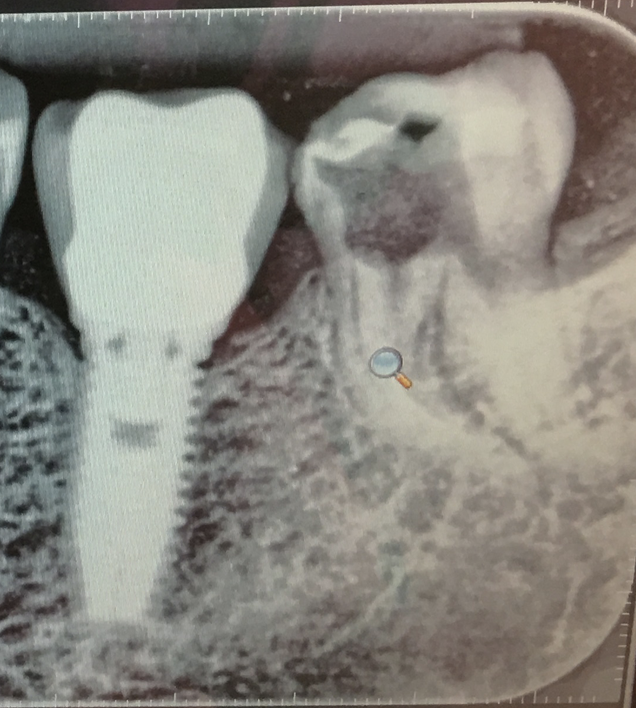

Какво се случва с кореновия канал, ако пълнежът излезе извън него?

Ако пълнежът излезе извън коренови канал, това може да създаде проблеми. Излизането на пълнежа може да доведе до инфекция или реинфекция на зъба. В такъв случай е необходимо да се консултирате със зъболекар, който може да прецени дали е необходимо повторно лечение на кореновите канали или други процедури за спасяване на зъба.